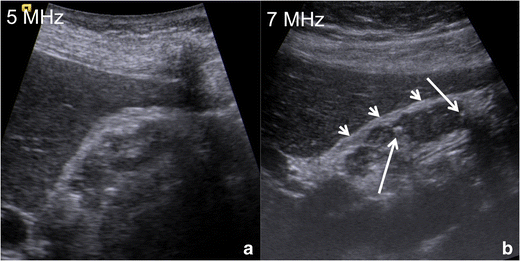

Fig. 6

US of gallbladder adenomyomatosis: use of different frequencies probes. In this patient with diffuse GA, the gallbladder wall is poorly evaluable by means of a conventional 5-MHz convex probe (a). Using a high-resolution 7-MHz linear probe (b) hyperechoic Rokitansky–Aschoff sinuses (arrows) can be highlighted within a diffusely thickened gallbladder wall; moreover, the serosa maintains sharp margins (arrowheads)

The use of high-frequency probes (Fig. 6) increases US accuracy in the diagnosis of GA. Indeed, GA often involves gallbladder fundus, which is usually unsatisfactorily evaluated by means of the classical 4–5-MHz convex probes; every suspicious finding in this area must be further investigated by means of higher frequency (7–9 MHz) linear probes for better characterization.